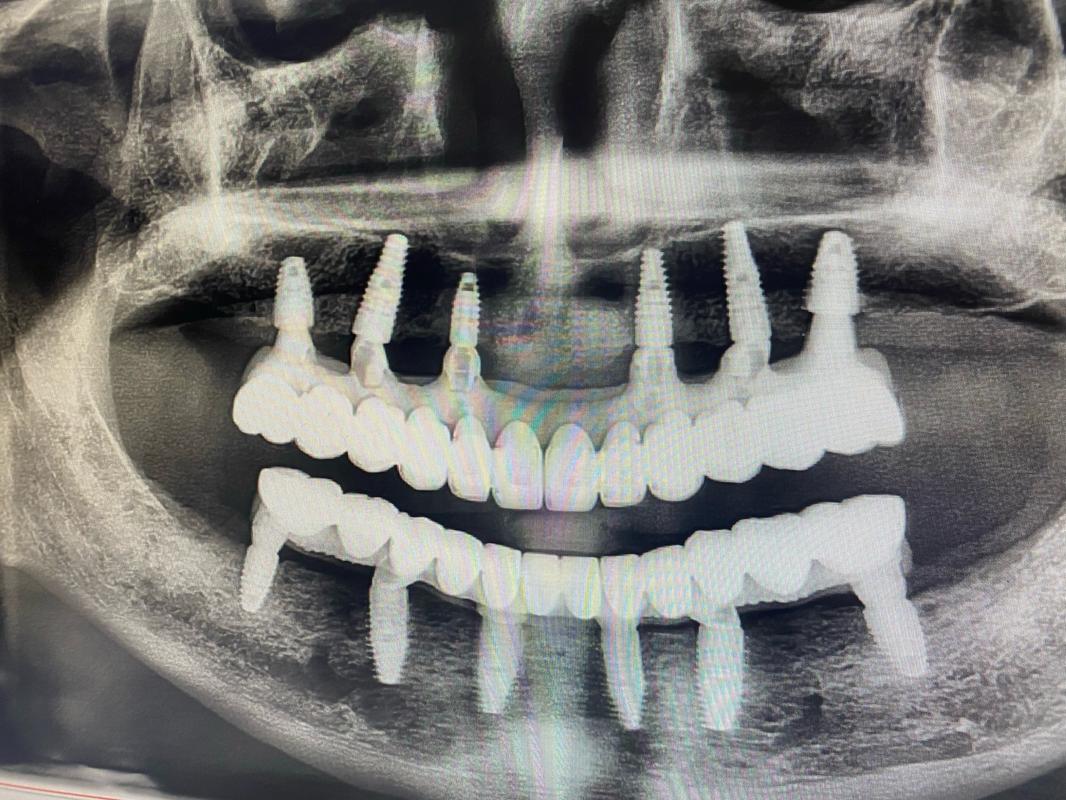

方案3:All-on-4/6半口/全口种植——“骨量不足也能半口牙重生”

针对半口/全口缺牙、牙槽骨严重萎缩的患者,传统种植可能需要大量植骨,而“All-on-4/6”技术通过“倾斜植入+即刻负重”,用4颗或6颗种植体支撑半口牙桥,避开骨量不足区域,实现“当天种牙、当天用牙”。

- All-on-4:在缺牙颌骨植入4颗种植体,其中后牙区种植体倾斜植入(避开上颌窦/下齿槽神经),利用现有骨量,戴入固定牙桥;

- All-on-6:增加2颗种植体,提供更强支撑力,适合骨量稍好或对咬合力要求高的患者。

优点:避免全口植骨,治疗周期短(1-3天),恢复咀嚼功能;缺点:对医生技术、种植体品牌要求高,费用相对较高。